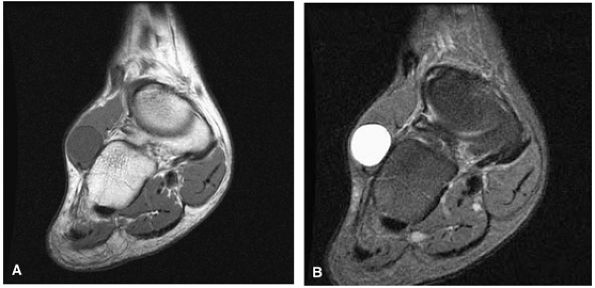

Fat-suppressed PD-weighted fast spin-echo sequences (FS PD FSE) in all three orthogonal planes (Fig. 5.1)

FIGURE 5.1 ● Visualization of tibiotalar articular surfaces using a coronal FS PD FSE sequence. Separation of the tibial and talar chondral surfaces is important in characterizing osteochondral lesions.